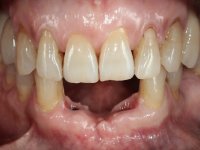

Female patient, 62 years old, smoker. 10 years ago, an implant had been placed in the area of teeth 41 and 42 to rehabilitate the lack of these two teeth with a two-element bridge. After the imaging exam, bone loss was observed next to the implant compatible with peri-implantitis. The buccal bone wall next to the implant showed extensive resorption, with the buccal surface of the implant in contact with the soft tissues and in a certain area a hole allowed the implant to be visualized through the gingival tissue. Teeth 42 and 32 already showed some mobility.